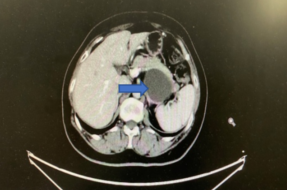

2019年9月复查盆腹增强CT:左肾前方结节较前增大,倾向为转移(图7)。CA-125指标正常。

图7 第五次复发CT检查结果